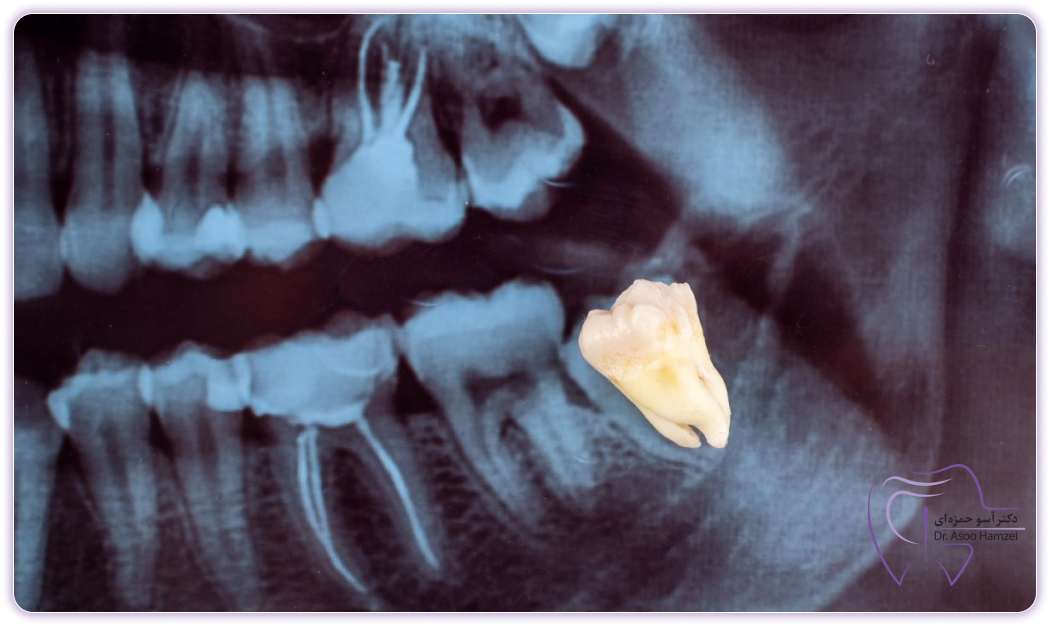

To check this infection, the dentist must examine your mouth and teeth clinically and using imaging. After examining the signs and symptoms, the dentist will determine how far the infection has progressed and what methods or drugs should be used to treat it. The best imaging methods include panoramic radiography (OPG), which is a two-dimensional image of the entire jaw and teeth, and CBCT imaging, which is a three-dimensional image.